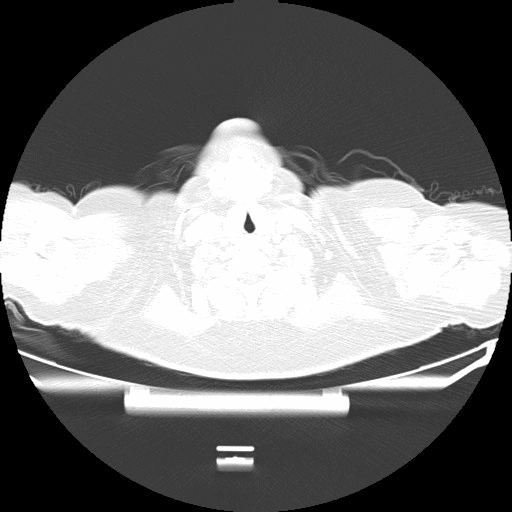

附图3 患者入院后第9天胸部CT(2021-06-21)

双上中肺可见部分小叶间隔增厚较前减轻